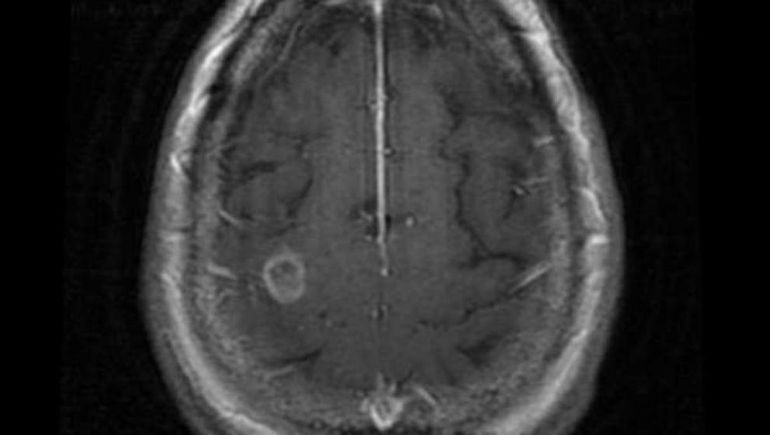

La infección ocurre cuando el agua que contiene la ameba entra en el organismo a través de la nariz. Una vez dentro, la ameba se desplaza hacia el cerebro y comienza a destruir el tejido. Trágicamente, en el 97% de los casos, esta infección resulta mortal, siendo esta la única especie de ameba que afecta de manera tan devastadora a los seres humanos.

Cuando la bacteria entra en el organismo, provoca una infección cerebral conocida como meningoencefalitis amebiana primaria (MAP), cuyos primeros síntomas se asemejan a los de la meningitis bacteriana. Estos síntomas suelen aparecer aproximadamente cinco días después de la infección.

Las personas infectadas pueden experimentar dolores de cabeza, fiebre, náuseas o vómitos. En etapas posteriores, pueden desarrollar rigidez en el cuello, confusión, falta de atención, pérdida del equilibrio, convulsiones y alucinaciones. La enfermedad progresa rápidamente y, en la mayoría de los casos, causa la muerte pocos días después de la infección.